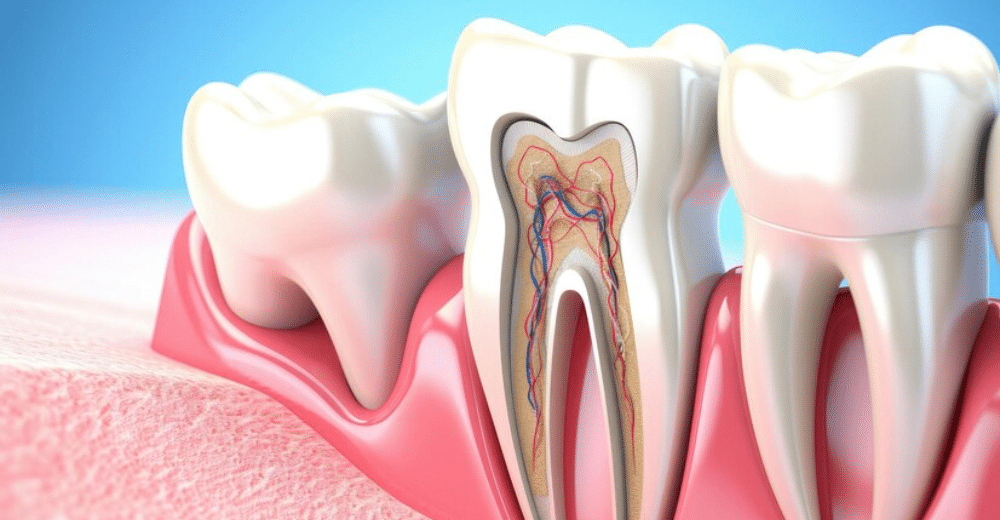

Some background will be helpful. As you will note from the illustrations, a space inside the tooth called the pulp chamber houses the root canal system and pulp — the living tissue that keeps the tooth vital (alive). The pulp includes blood vessels, nerves and connective tissues, and, during childhood, creates the surrounding hard tissues of the tooth. Endodontic treatment (“endo” – inside; “dont” – tooth), commonly known as root canal treatment, is needed when the pulp becomes inflamed or infected. The causes could be deep tooth decay, repeated dental procedures on one tooth (replacing a large filling, for example), or traumatic damage such as a crack, chip or even a root fracture. Gum disease can also give rise to root canal problems necessitating root canal treatment. Any of these issues can result in acute inflammation of the pulp, which causes swelling and pressure inside the tooth (that has nowhere to go), leading to tooth pain and, eventually, irreversible damage to the pulp.

Once the pulp dies, the pain may subside initially, sometimes to return as an acute (painful) infection spreading into the periapical tissues (“peri” – around; “apex” – end), particularly the bone. It could also become a chronic (long-standing) infection with symptoms ranging from mild to severe.